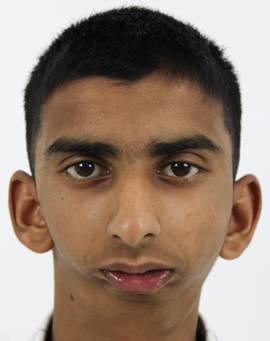

Let us take you through the journey of this young 18 year old boy who had come to us with a complaint of reduced mouth opening and a very short lower jaw. He has had this condition since childhood and has difficulty in eating food and talking and more sadly, has been a victim of bullying at school along with the other functional difficulties mentioned before.

Below are the post-operative photos of the patient on the 8th day post surgery, with the surgical scars noted in the preauricular and perimandibular regions. A marked improvement in his mouth opening from literally one finger mouth opening to around 30mm post surgery was achieved. Along with this, a drastic improvement in his profile is seen.